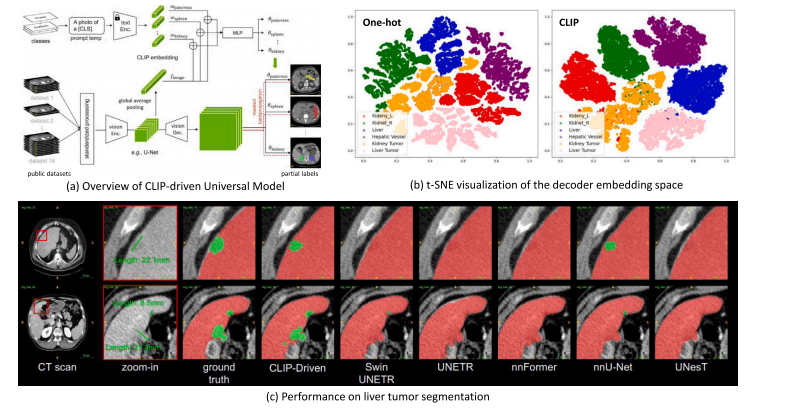

Fig. 13. (a) Overview of CLIP-driven segmentation model for universal segmentation (Liu et al., 2023g). (b) t-SNE visualization of the decoder embedding space between one-shottask encoding and CLIP label encoding. (c) Performance on liver tumor segmentation (green for tumor and red for organ).

图13:(a)用于通用分割的由对比语言-图像预训练模型(CLIP)驱动的分割模型概述(刘等人,2023g)。(b)单样本任务编码和解码器嵌入空间与CLIP标签编码之间的t分布随机邻域嵌入(t-SNE)可视化。(c)肝脏肿瘤分割的性能表现(肿瘤为绿色,器官为红色)。